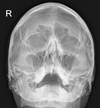

critique

petrous too low, by 10 deg (neck is extended) OML not perpendicular